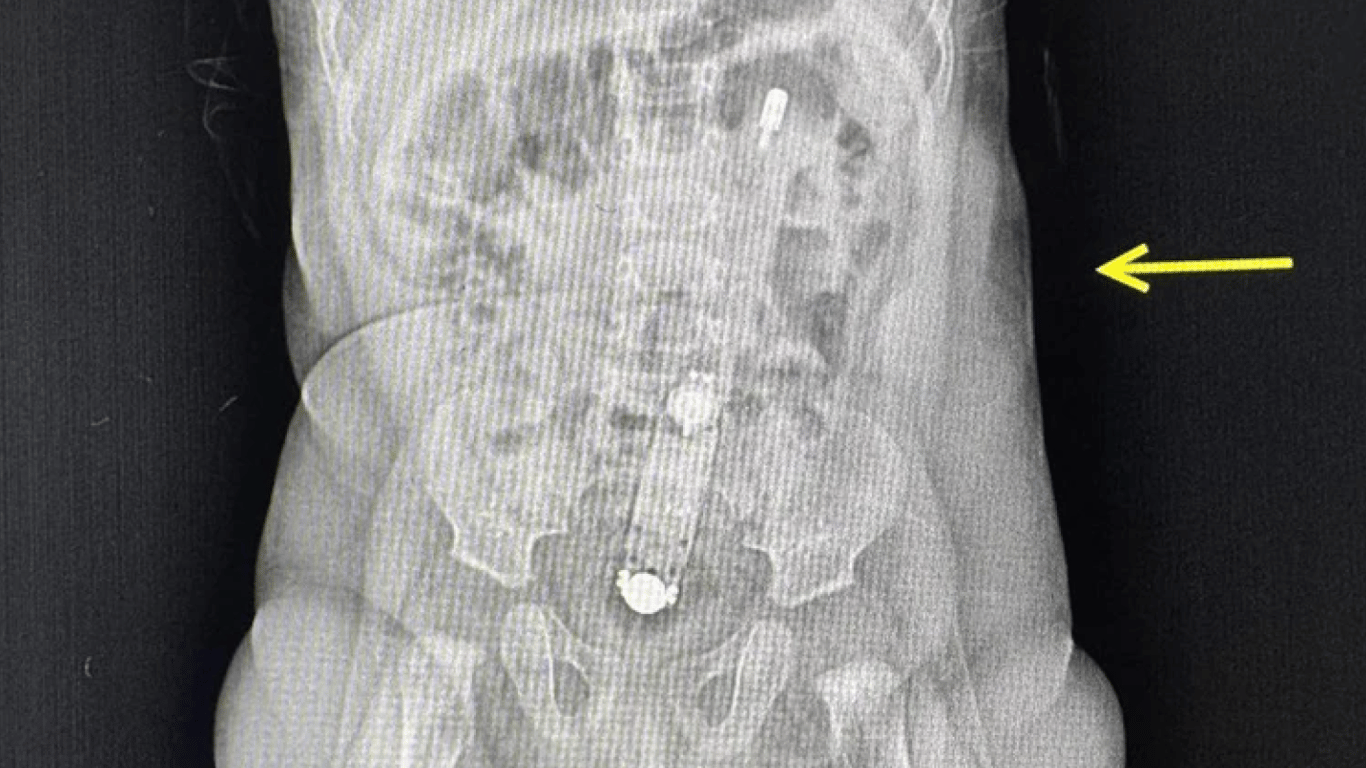

Рентген младенца. Фото: Волынское областное медобъединение защиты материнства и детства

В Луцке из-за самолечения младенец оказался в больнице. Врачи обнаружили в толстом кишечнике шестимесячной девочки электронный термометр, который родители использовали в попытках лечения запора.

8 октября бригада экстренной медицинской помощи транспортировала маму с ребенком из Камня-Каширского в Волынскую областную детскую клиническую больницу в Луцке. Врачи, проведя рентгеновское обследование, обнаружили термометр, который можно было прощупать при осмотре живота ребенка.

Мать младенца объяснила, что пыталась сделать клизму с помощью термометра, смазанного растительным маслом. К сожалению, это привело к тому, что прибор полностью попал в кишечник ребенка.

Для извлечения термометра медицинские работники применили эндоскоп, избегая хирургического вмешательства.

"Достать прибор было очень непросто. Действовать нужно было очень осторожно, чтобы не травмировать младенцу анус и внутренние органы. Самостоятельно градусник выйти не мог, вместо этого мог перфорировать кишечник или в дальнейшем спровоцировать кишечную непроходимость", — пояснили врачи.